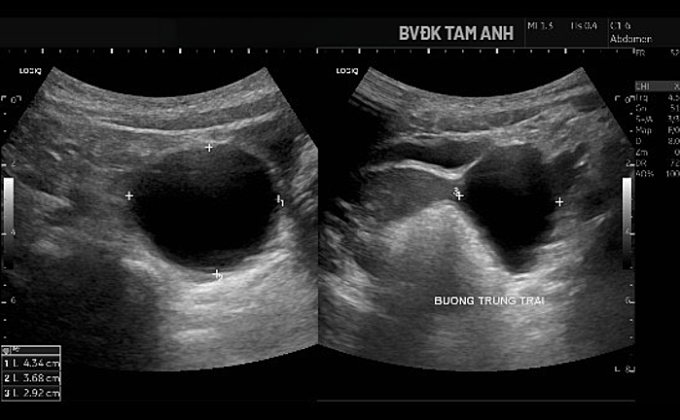

Ngoài ngực phát triển, bé Huyền chưa xuất hiện dấu hiệu dậy thì khác. ThS.BS Đỗ Tiến Sơn, khoa Nhi, Bệnh viện Đa khoa Tâm Anh Hà Nội, ghi nhận tuyến vú của trẻ đã phát triển ở giai đoạn Tanner B3 - giai đoạn bắt đầu xuất hiện mô tuyến vú nhanh và rõ. Buồng trứng trái có nang lớn kích thước khoảng 43x37x29 mm, thành mỏng, chứa dịch trong, bên trong có nang nhỏ. Tổn thương được xếp loại ORADS 2, nguy cơ ác tính thấp. Chụp MRI xác định nang buồng trứng trái lành tính. Kết quả X-quang đánh giá tuổi xương chưa tăng, hiện phù hợp với tuổi thực của bé.

Hình siêu âm cho thấy nang buồng trứng phì đại. Ảnh: Bệnh viện Đa khoa Tâm Anh